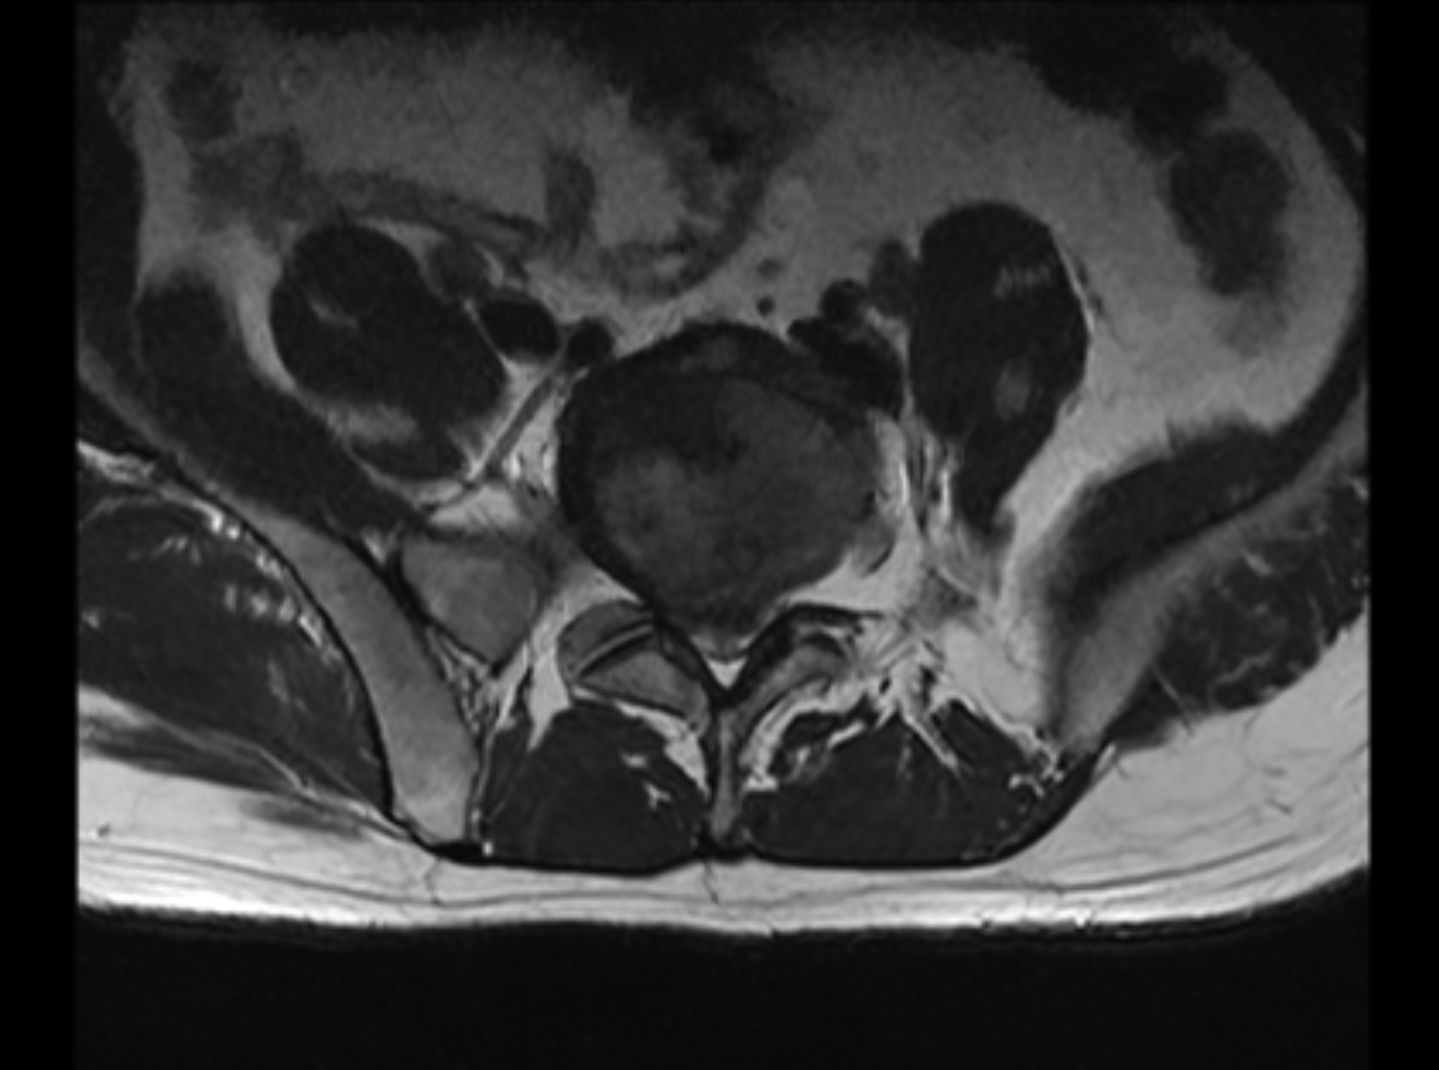

MR报告

放射学表现

腰椎生理曲度变直 , 椎体排列尚整齐 ; 腰3椎体偏前侧见 0.9x 1.4cm的椭圆形较高信号灶 , 压脂后信号减低 , 余所示 椎体信号未见明显异常 , 各椎体边缘骨质增生改变 , 骨性 椎管未见明显狭窄 ; 腰5/聶1椎间隙变窄 , 相对缘终板面略 毛糙 , T2WI/FS信号稍高 ; 腰5/髓1椎间盘向后明显突出 致局部椎管变窄 , 马尾终丝受压 ; 腰3/4、4/5水平椎间盘 向周围轻度膨隆 , 硬膜囊略受压 ; 余圆锥、马尾形态、信 号未见明显异常。

放射学诊断

1.腰5/艇1椎间盘明显突出 , 致局部椎管变窄。 2.腰3/4、 4/5椎间盘轻度膨隆。 3.腰3椎体异常信号灶 , 考虑脂肪沉 积可能 , 请随诊。 4.腰椎轻度退变 , 生理曲度变直 ; 腰5/ 融1椎体相对缘终板炎改变。